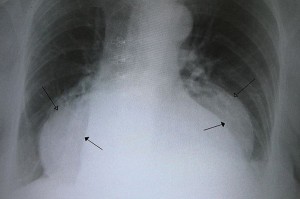

o Electrocardiogram (ECG)

o Chest x-ray

o Barium swallow or upper GI x-ray